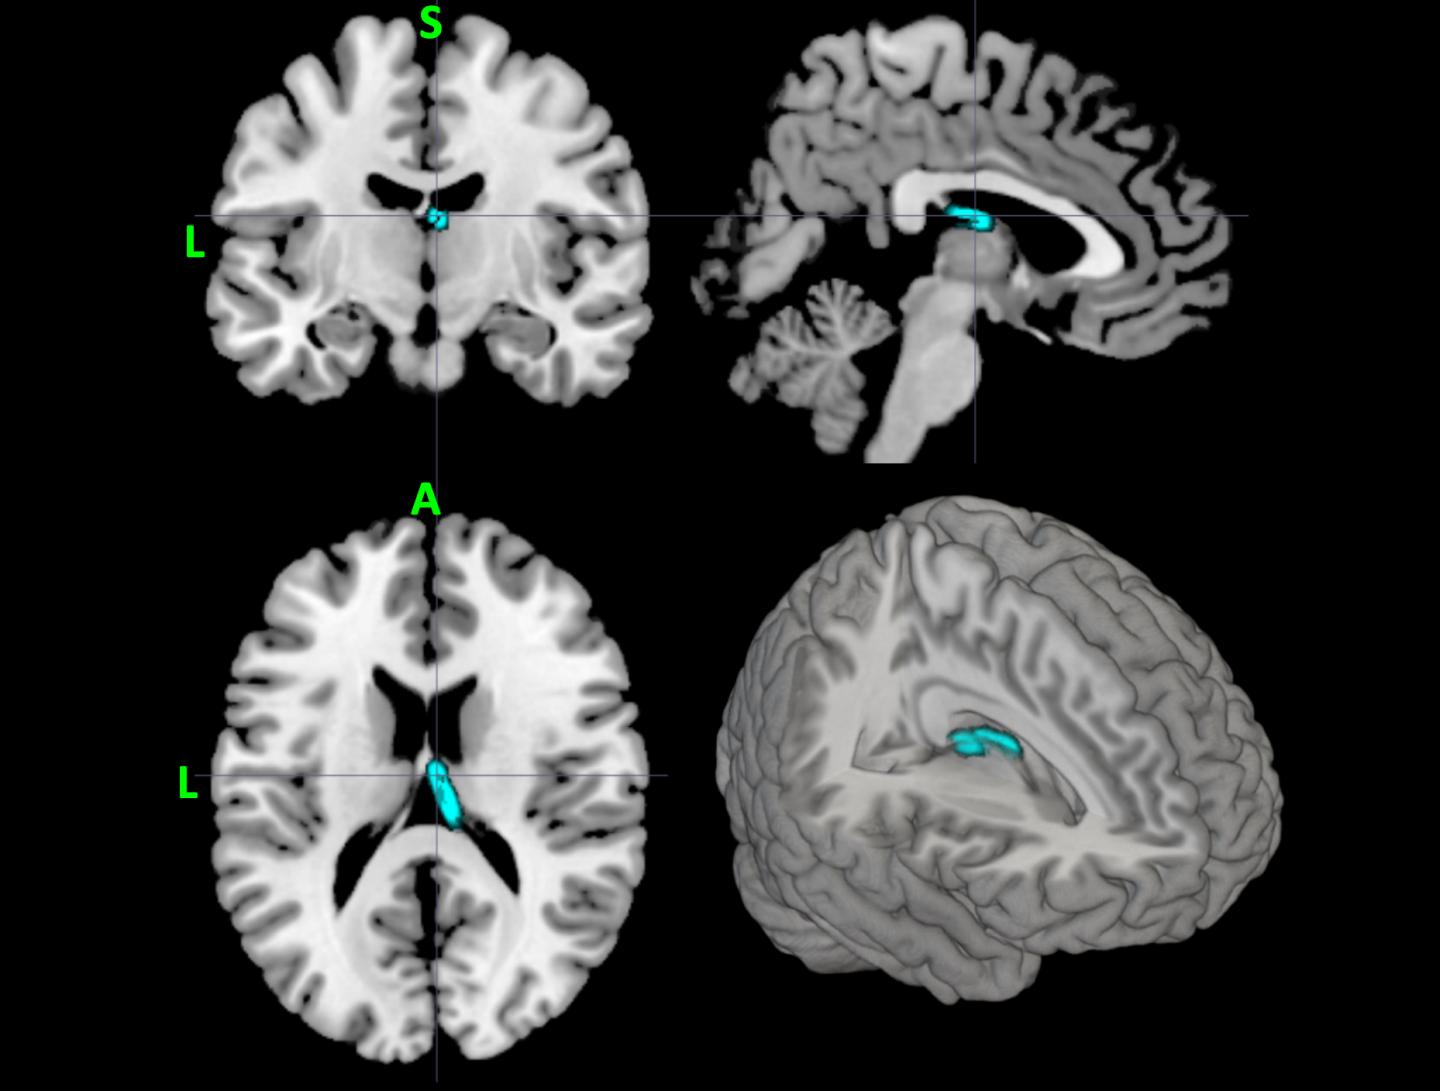

Για να γίνει όμως αυτό χρειάζεται ένας υπερυπολογιστής στο Τέξας Advanced Computing Center (TACC) για να εκπαιδεύσει έναν αλγόριθμο μηχανικής μάθησης που μπορεί να εντοπίσει ομοιότητες ανάμεσα σε εκατοντάδες ασθενείς που χρησιμοποιούν Μαγνητική Τομογραφία (MRI) του εγκεφάλου, δεδομένων γονιδιωματικής και άλλους σχετικούς παράγοντες, για να παρέχουν ακριβείς προβλέψεις του κινδύνου για τα άτομα με κατάθλιψη και το άγχος.

Οι ερευνητές έχουν από καιρό κάνει μια προσέγγιση των ψυχικών διαταραχών, εξετάζοντας τη σχέση μεταξύ της λειτουργίας και της δομής του εγκεφάλου σε δεδομένα νευροαπεικόνισης.

Διαπιστώθηκαν λεπτές συνδέσεις μεταξύ διαφορετικών τμημάτων του εγκεφάλου και έχτισε ένα μοντέλο που εκχωρεί νέα παραδείγματα για μία ή την άλλη κατηγορία.